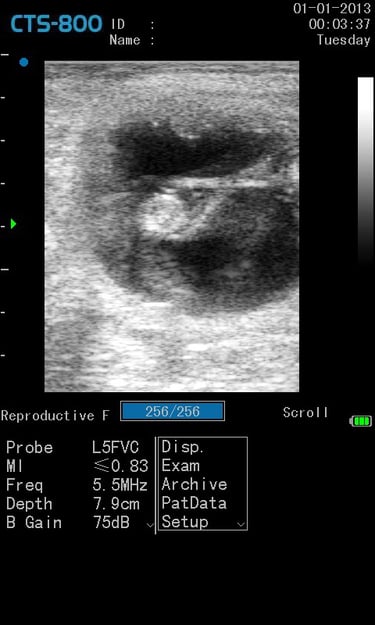

Gynécologie